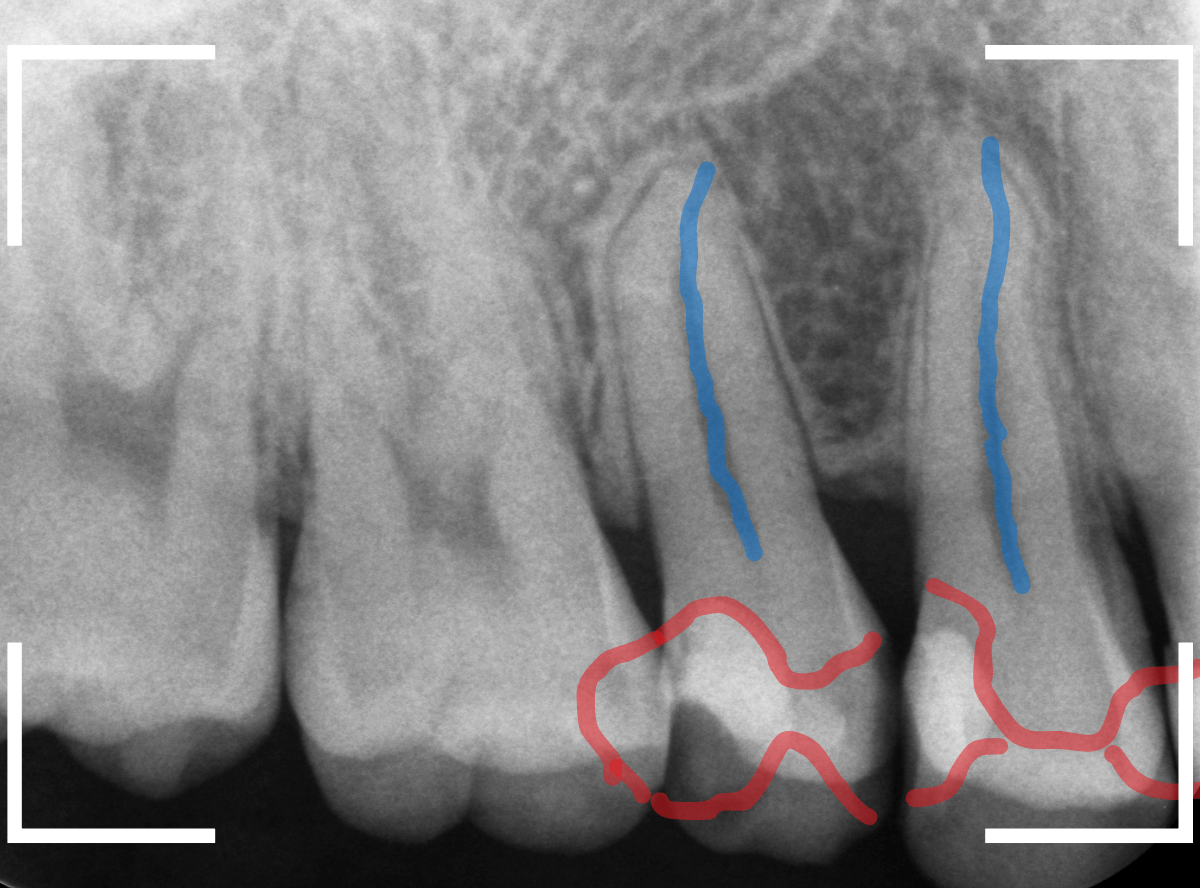

レントゲン写真です。

レジンの下が虫歯になっているのがわかります。

レントゲン写真で確認します。

青い線が歯の神経、赤い線が虫歯です。

おやしらずがあった際にはわかりづらかったですが、歯の後ろ側のおやしらずが重なっていたところが虫歯になっているのがわかります。

おやしらずが原因で、このように手前の歯が虫歯になってしまう事が多いために、抜歯を勧められる事が多いのです。

そして、虫歯の部分におやしらずが被さっていたために、しみる症状などを感じなかったのです。